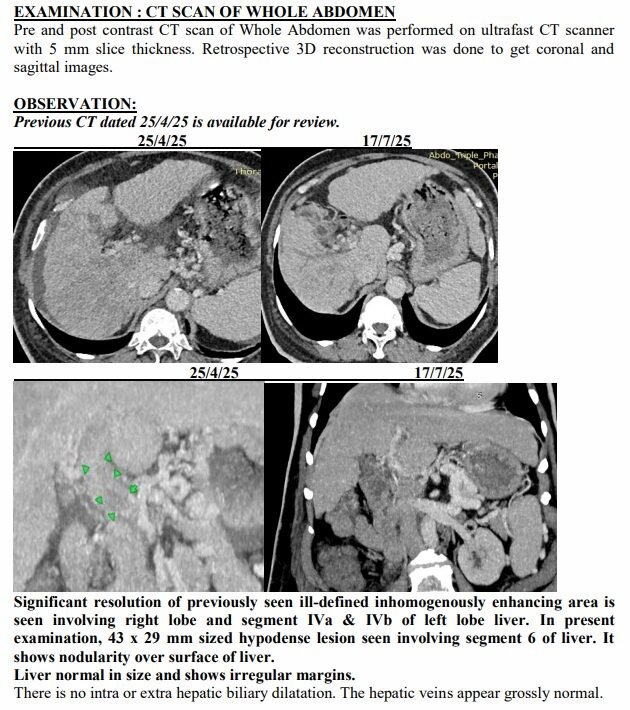

Surat (Gujarat) [India], August 22: On a hot April afternoon in Surat, the Patel family sat in a crowded hospital waiting room, clutching a CT scan report that felt heavier than paper. The words were sharp, merciless: advanced liver cancer, spread across both lobes, blocked veins, fluid buildup, bone changes. For 74-year-old Ravjibhai (name changed), the doctors spoke plainly: there was no cure left, only comfort care.

Yet just three months later, on another afternoon in July, the same family stared at a different scan. The tumours had shrunk to one patch. Blood was flowing again. The swelling was gone. Even the alarming tumour marker that had shot up to 1,000 ng/mL had fallen to 10, back in the safe zone. For a man who had been fading fast, it was a turnaround no one in the room dared to predict.

The July scan sealed what they were already feeling at home. The many shadows in his liver had shrunk into one. His abdomen, once swollen with fluid, was flat again. His numbers, which had scared even seasoned oncologists, were suddenly within range.